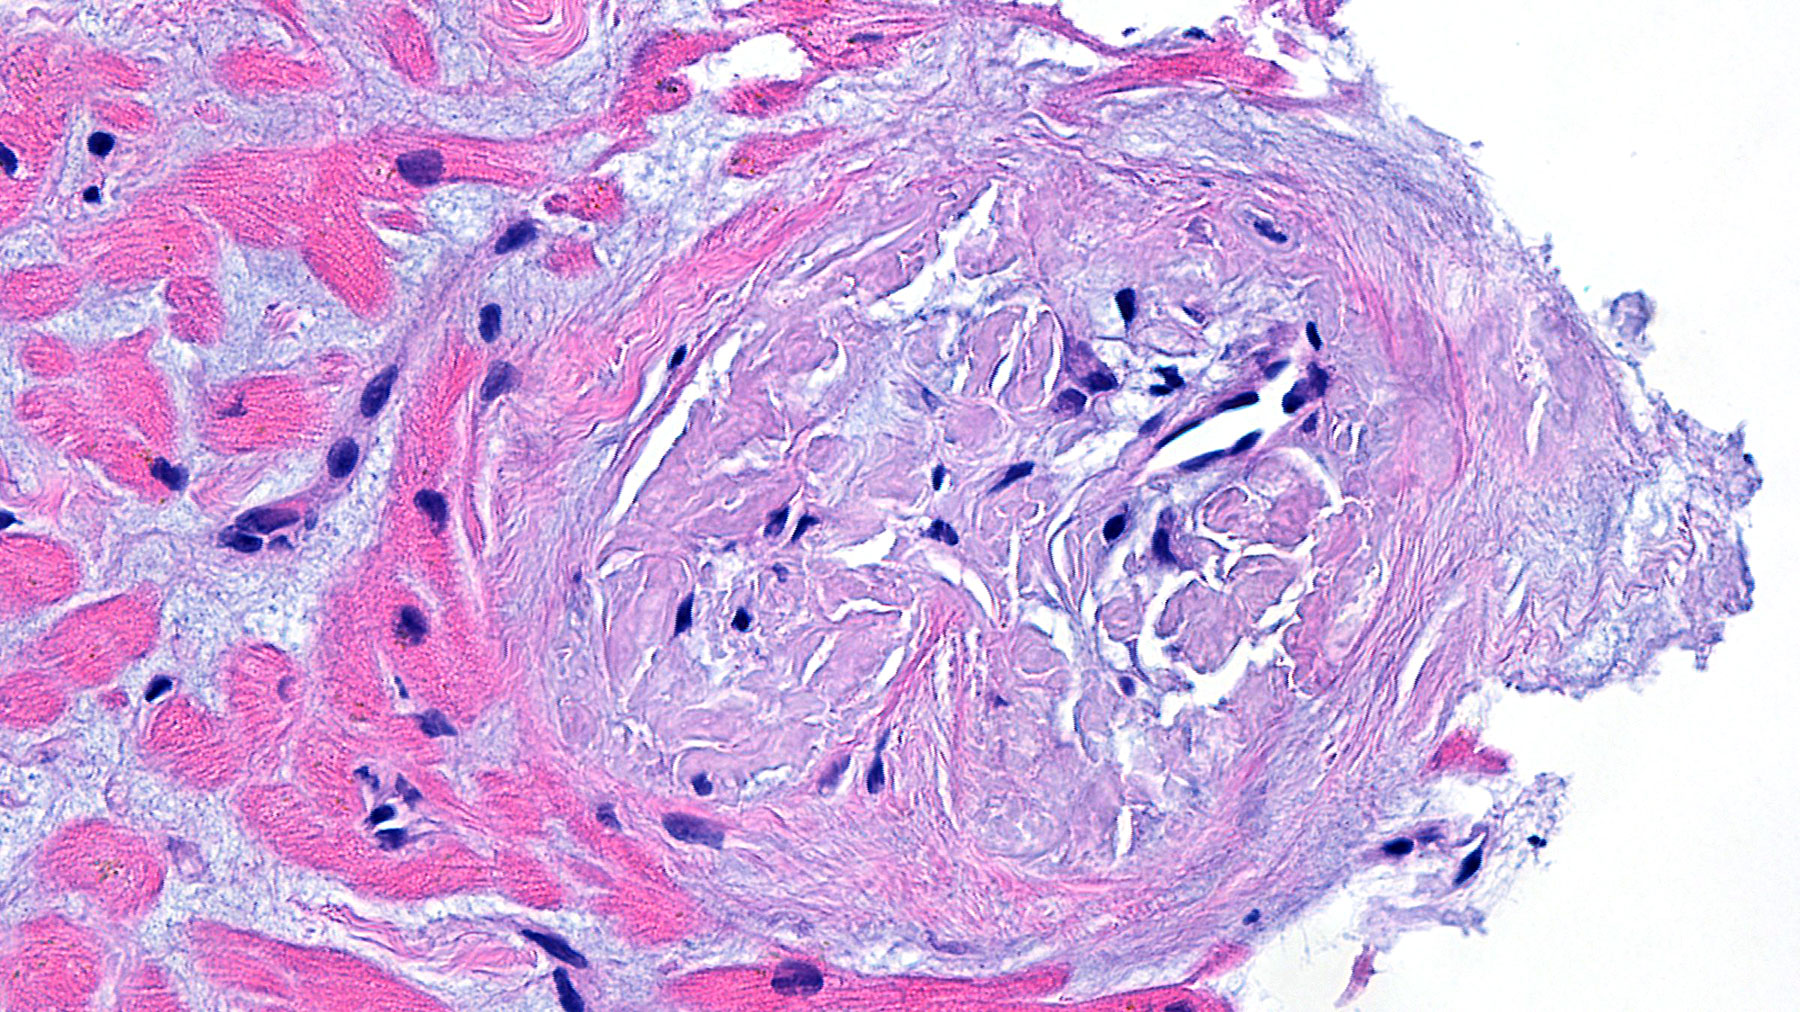

Figure A. H&E x20

Histology: A heart biopsy was performed and H&E sections (Figures A & B) show myocardial tissue with unremarkable cardiomyocytes and mild to moderate interstitial fibrosis, confirmed by trichrome staining (Figures C and D). The small vessels show moderate wall thickening with accumulation of smudgy, light eosinophilic material with cracking appearance, which stains light purple with the trichrome staining. Congo red staining (Figure E) viewed under polarized light shows apple-green birefringence consistent with amyloid deposits. Electron microscopic examination (Figures F and G) reveal cardiomyocytes and vascular structures surrounded by a fibrillary material (Figure G) consistent in size and appearance with amyloid (n 5-15 nanometer).